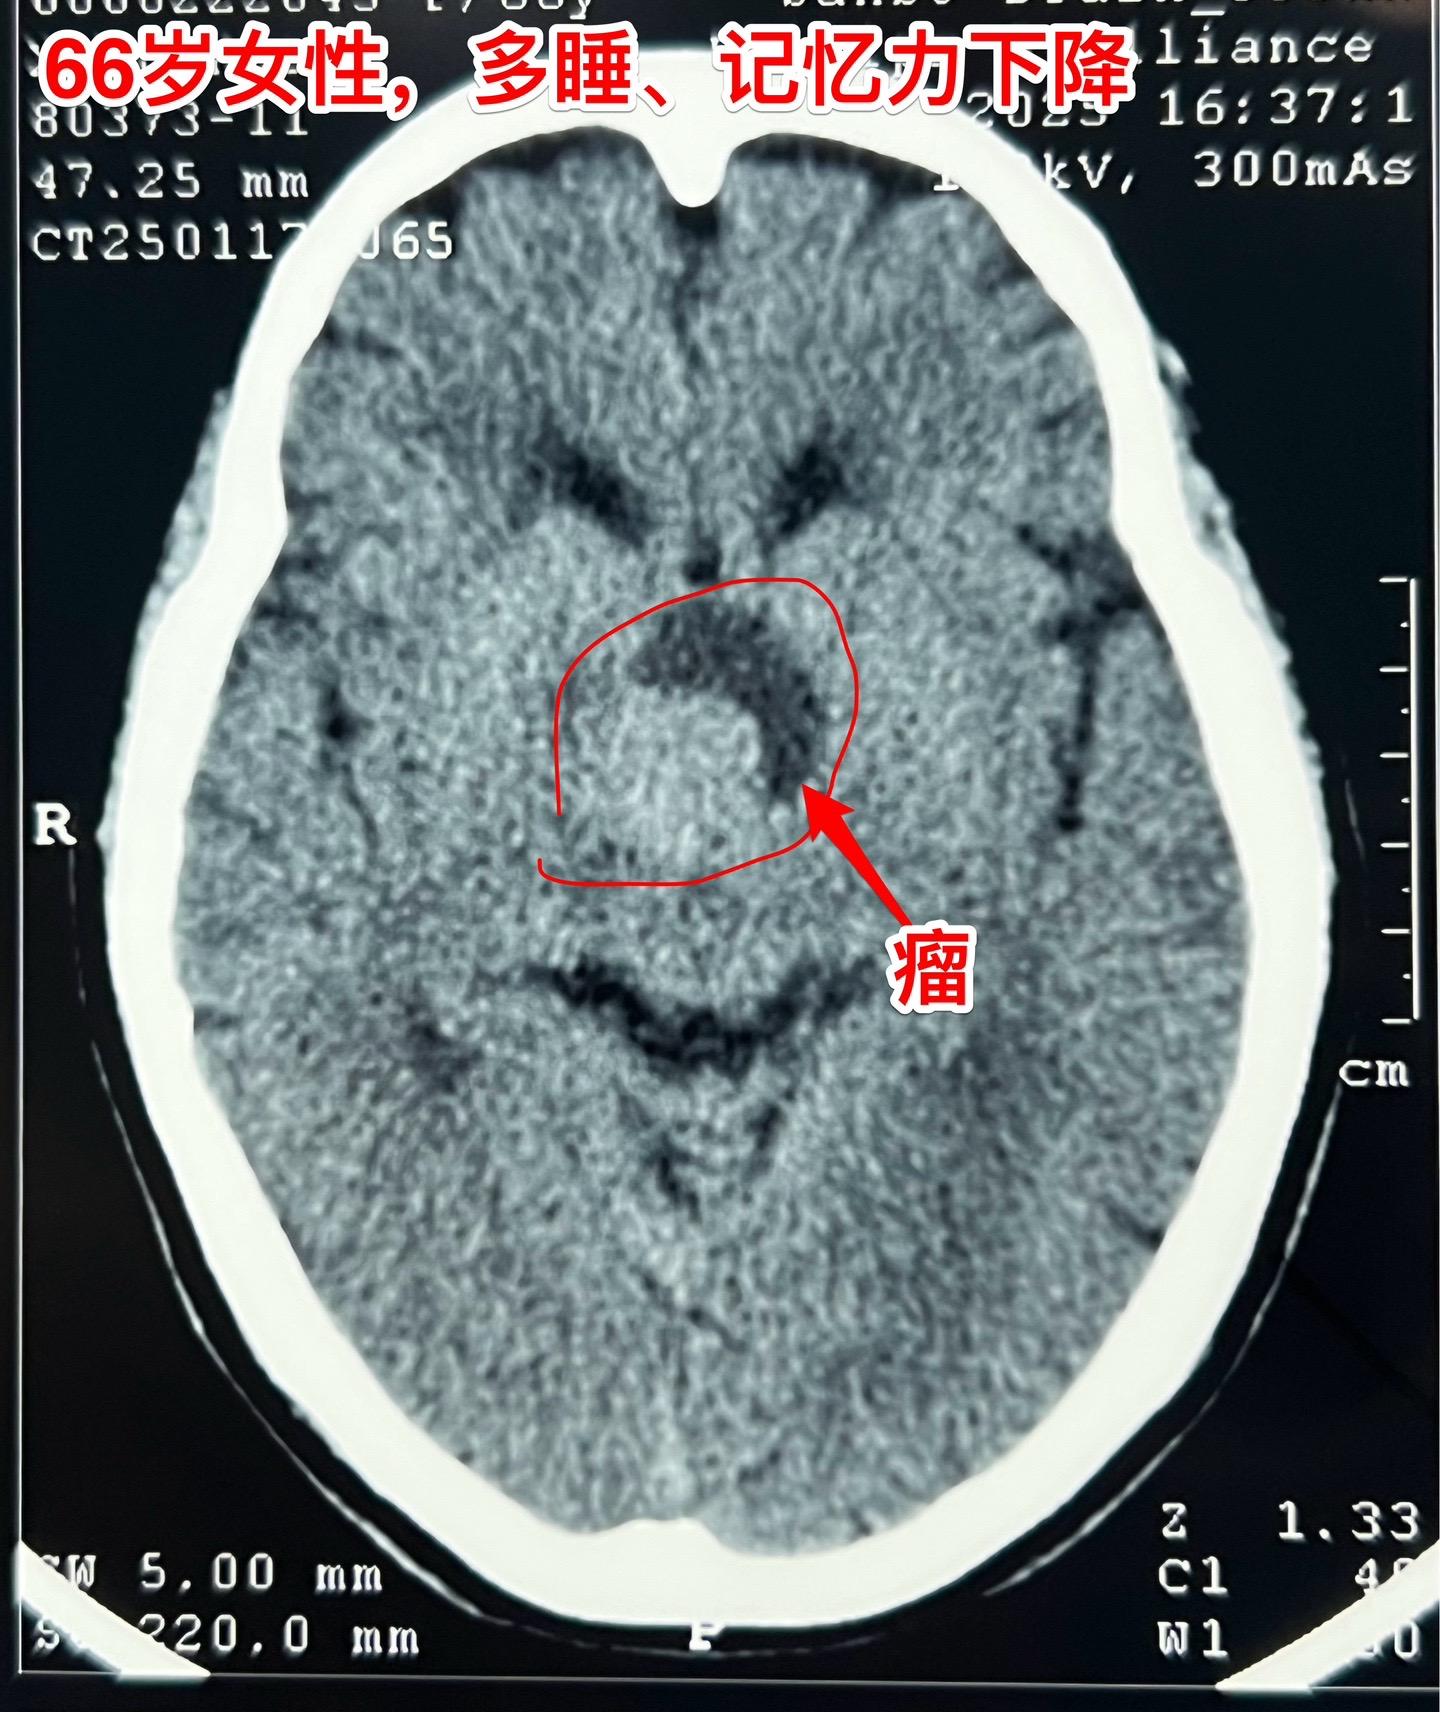

是颅咽管瘤吗?鞍区肿瘤的定性诊断是很难的。66岁女性,泰州人。因为多睡、记忆力下降在外院检查脑部发现脑部肿瘤。病人的多睡症状越来越严重。肿瘤位于鞍上区域,而且伴有脑积水。外院怀疑是颅咽管瘤?或者是别的肿瘤? 病人曾经在上海就医过,因担心手术风险,通过三博脑科医院院长找我咨询,随后决定到我院作手术。 1月24日作了开颅手术(这是我科春节前的最后一个择期手术),手术中发现肿瘤的性状不符合乳头型颅咽管瘤,分两次取标本送快速冰冻病理检查,报告考虑是胶质瘤。 下丘脑胶质